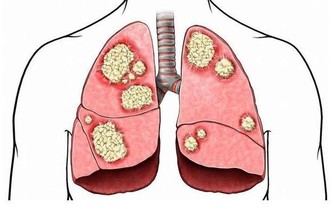

懶得刷牙不僅會導致口腔潰瘍、牙齦出血、牙周病,口腔細菌還會跑到咽喉部,增加老人患感冒和吸入性肺炎的風險。

△調節方法:懶得刷牙的人,患癌幾率比一天刷兩次牙的人高2.5倍。而漱一次口能減少20%的口腔細菌,刷一次牙可減少70%左右。中老年人牙齒健康的標準則是到了80歲,還有20顆能夠咀嚼食物的牙齒。要想避免「老掉牙」,必須堅持每天早晚刷牙的好習慣。